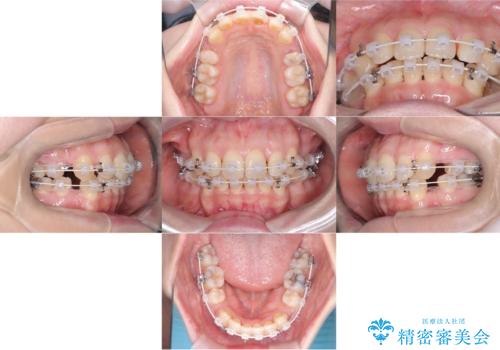

- 矯正装置

- ワイヤー(審美装置)

上下左右の4番(第一小臼歯)を抜歯をし審美ワイヤー装置で治療を行いました。

抜歯矯正により歯列のデコボコ(叢生)が改善し、前歯の突出も解消されたことで口元が下がり、すっきりとした印象となりました。